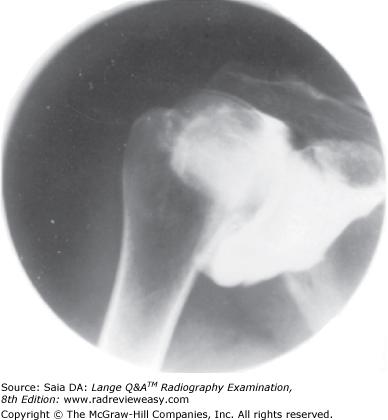

In which position of the shoulder is the outline of the greater tubercle superimposed on the humeral head?

A AP

B External rotation

C Internal rotation

D Neutral position

-The external rotation position is the true AP position and places the greater tubercle in profile laterally and places the lesser tubercle anteriorly. The internal rotation position demonstrates the lesser tubercle in profile medially and places the humerus in a true lateral position; the greater tubercle is seen superimposed on the humeral head. The epicondyles should be superimposed and perpendicular to the IR. The neutral position places the epicondyles about 45 degrees to the IR and the outline of the greater tubercle superimposed on the humeral head.